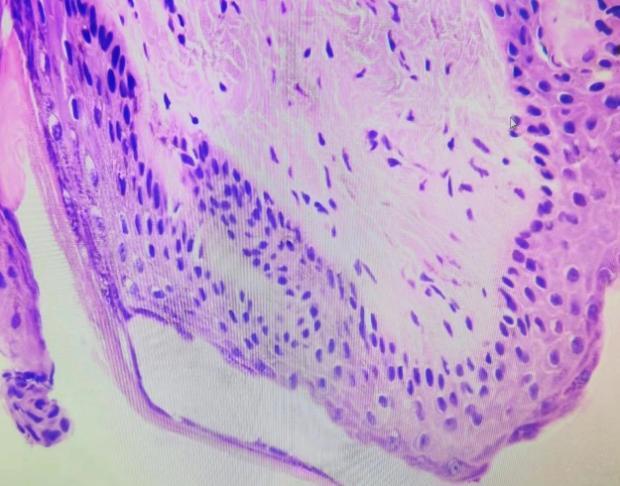

在采耳过程中发现,他的耳洞里竟然长了个“瘤子”,一触即痛,还伴有轻微出血……小徐急忙前往福建省妇幼保健院耳鼻喉科就诊。医生为他使用视频耳镜进行检查,考虑为外耳道乳头状瘤,建议立即手术切除治疗。

完善相关术前检查后,医生为小徐在局麻下快速完成外耳道肿物的切除手术,术后病理证实确为乳头状瘤。术后患者感觉良好,第二天便重返岗位上班。

外耳道乳头状瘤,又称外耳道尖锐湿疣,是一种发生于外耳道软骨皮肤的良性肿瘤,多因外耳道的鳞状细胞或基底细胞长期受到刺激而发生增殖。我国南方较多见,且好发于男性。